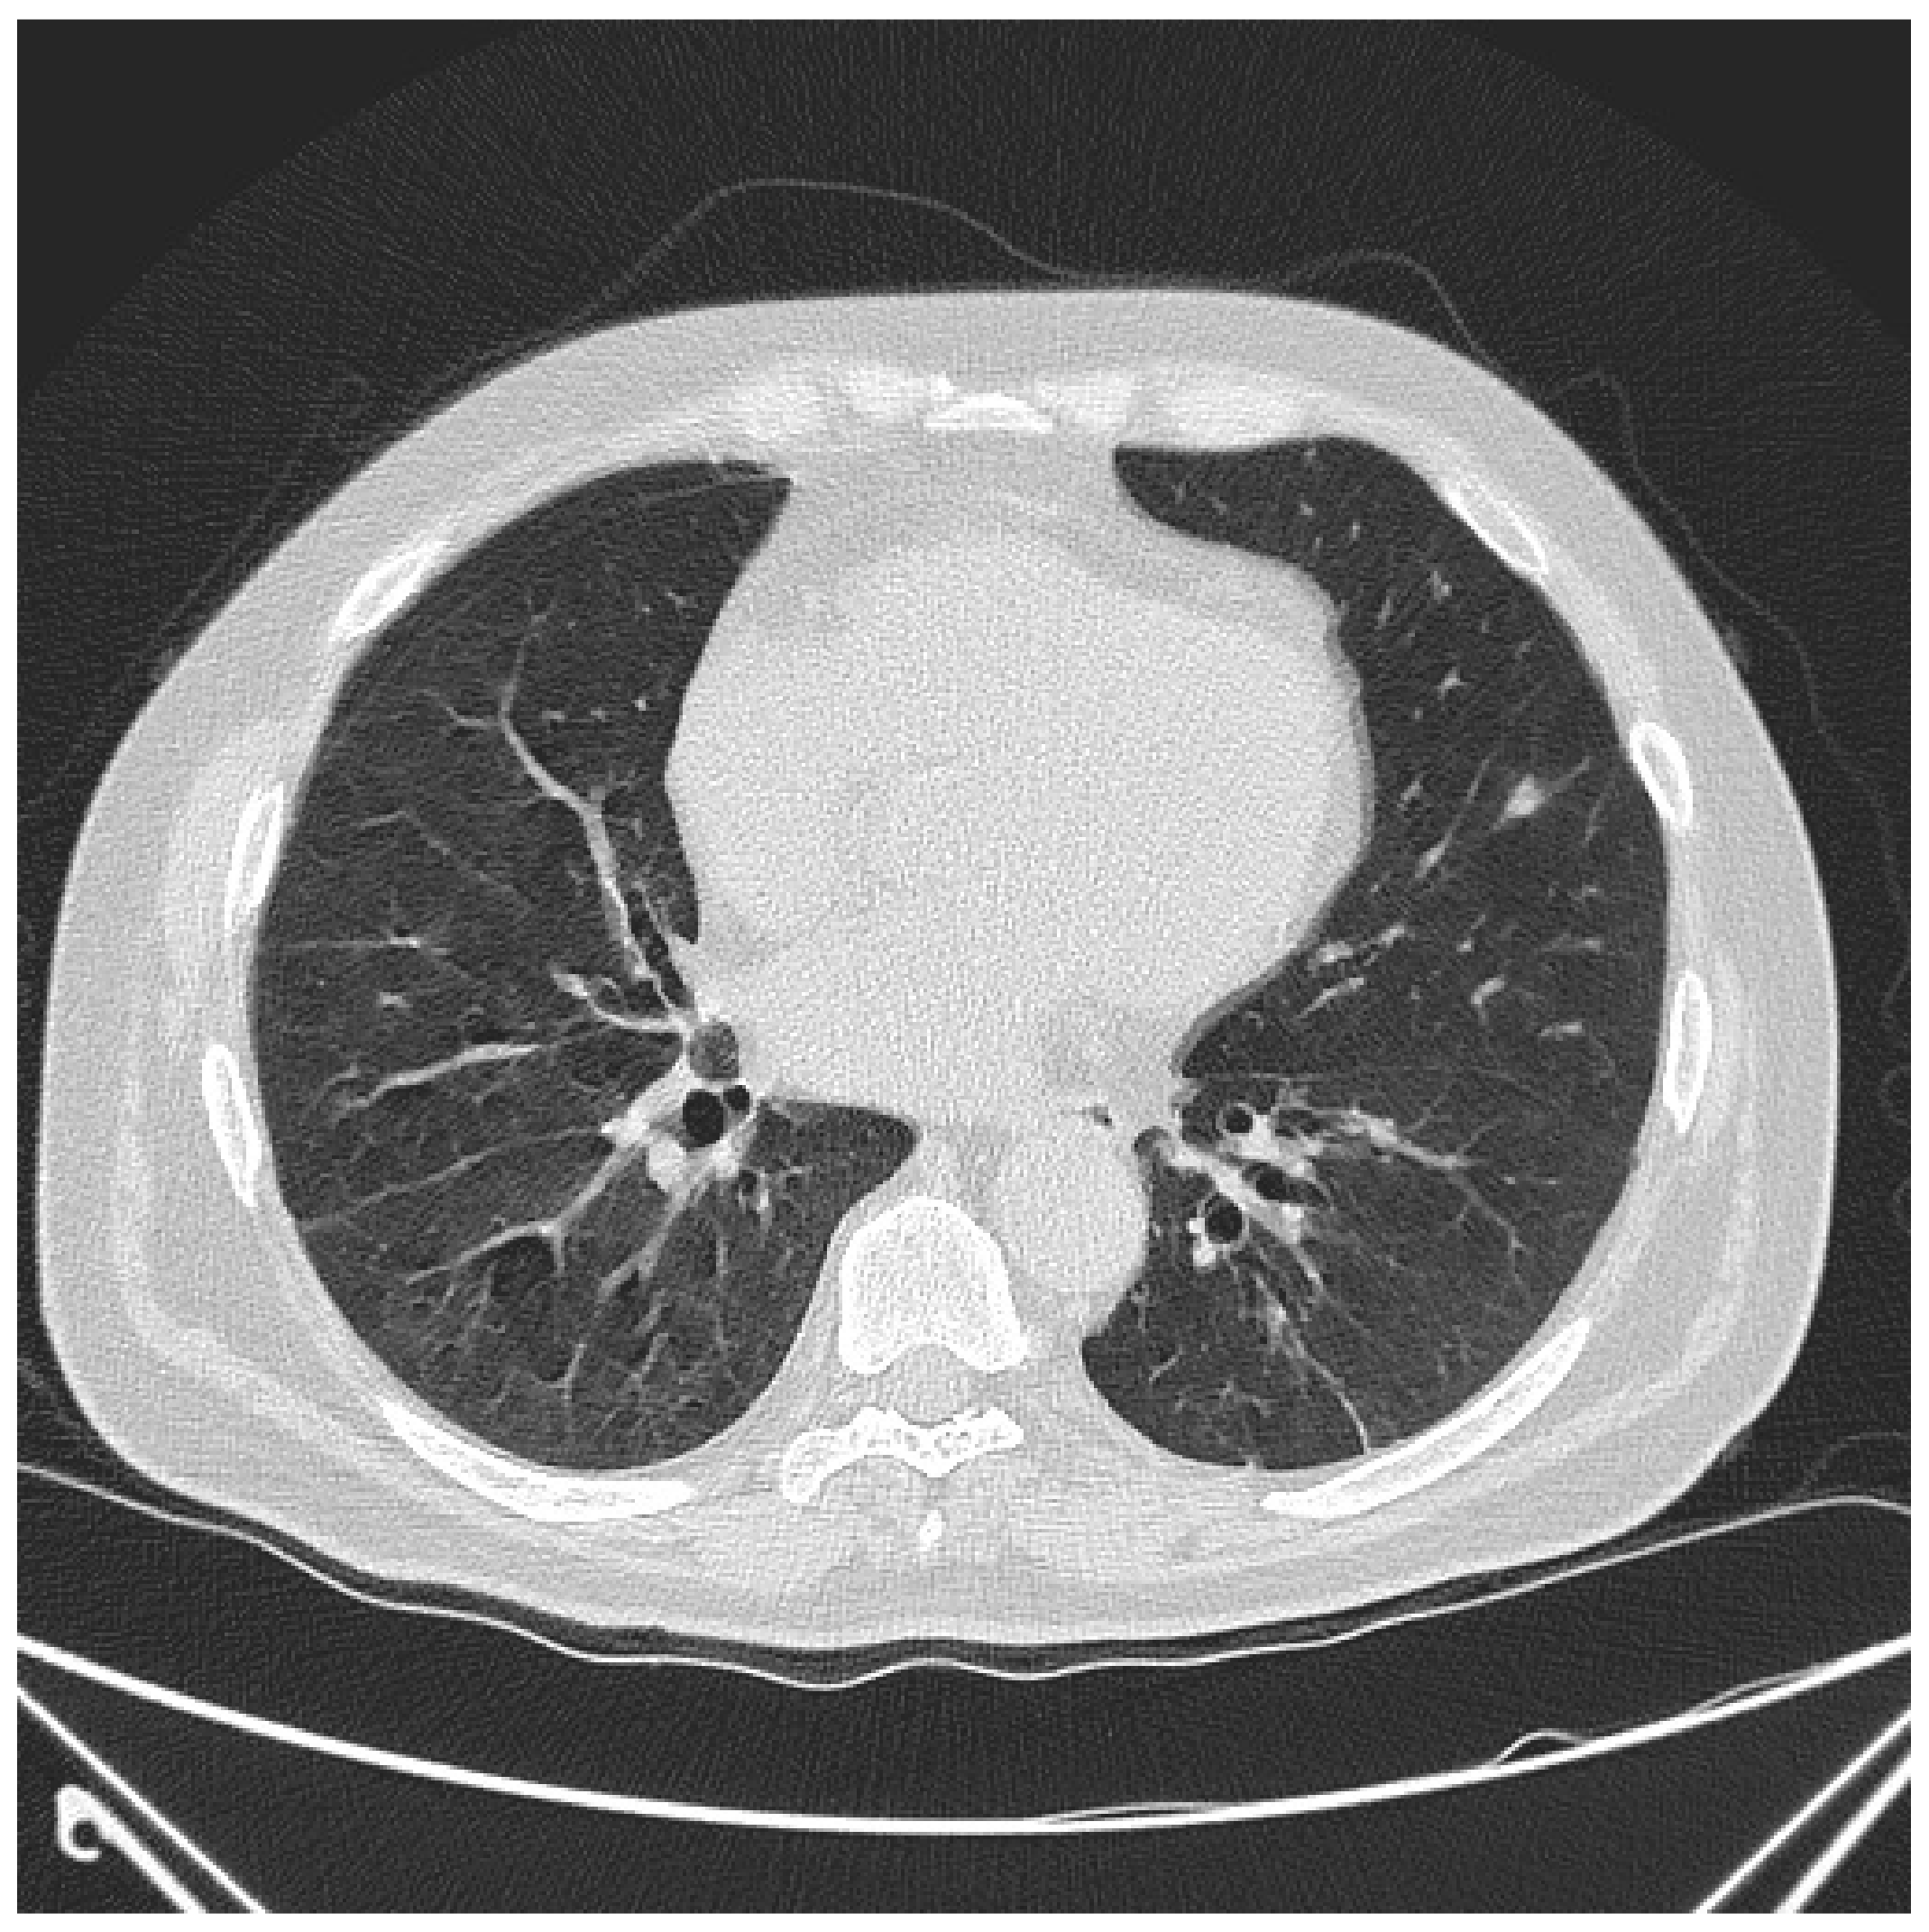

2.1. Case Report 1

6.2. Histopathologic and Radiographic Findings in Myositis-Associated ILD